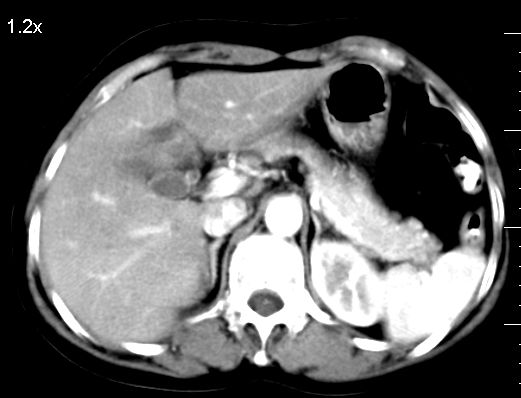

标题: CT10752:F,52岁,反复上腹部疼痛,平扫+增强. [打印本页]

f、52岁,反复上腹部疼痛2年。肺结核病史10多年,胸片双上肺结核纤维化。

ct表现:

肝大小形态未见异常,肝内外胆管无扩张,肝s8段见一动脉期明显血管样强化结节,门脉期呈高密度,延迟期呈等密度,胆囊不大,增强扫描见胆囊及胆囊颈管壁增厚,有强化。

双肾灌注良好,代谢增快,动脉期肾盂见造影剂,左肾下极背侧见一略低密度病灶,延迟期见似不强化囊肿,双侧肾上腺未见异常。

胰腺及脾未见异常。肾门水平腹膜后见小淋巴结。腹腔未见积液征象。

诊断:

1、胆囊炎(轻度)。

2、肝s8段结节,考虑小血管瘤。

3、左肾下极低密度灶,考虑囊肿可能性大,建议随访,除外小肾癌(无强化可以基本除外)。

4、目前ct表现尚不能解释患者上腹部疼痛,建议上消造影检查,除外胃炎等疾患。